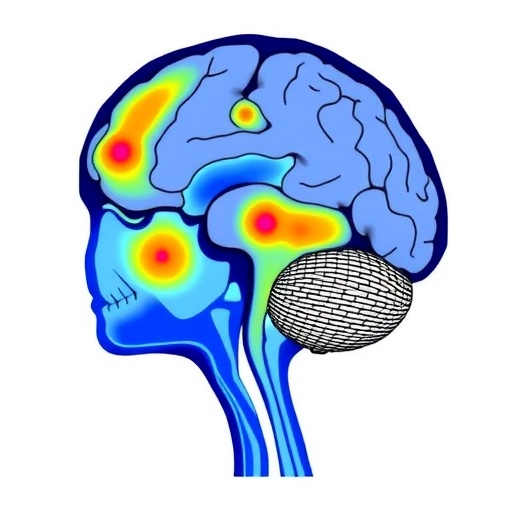

Postural control involves a complex interplay of sensory inputs, central processing, and musculoskeletal responses. It requires the integration of vestibular, somatosensory, and visual systems to maintain balance and orientation against gravitational forces. In children with spastic cerebral palsy, damage to brain areas mediating these sensory and motor processes might compromise this integrative capacity. The study systematically analyzed lesion patterns, including periventricular leukomalacia, cortical and subcortical injuries, and their spatial distribution relative to motor and sensory cortical regions. Intriguingly, specific lesion topographies were found to correspond with distinct postural control profiles, suggesting personalized neural substrates for balance impairments.

Beyond neuroanatomical insights, this research brings to light sophisticated neurophysiological mechanisms implicated in posture regulation. Lesions affecting the corticospinal tracts and secondary motor pathways were associated with diminished reflex modulation and impaired anticipatory postural adjustments. Moreover, damage to parietal regions—the hubs for sensory integration and spatial awareness—correlated strongly with increased postural sway and instability. These findings implicate disrupted sensorimotor integration as a driver of postural deficits. Such mechanistic understanding is paramount for developing targeted therapies that transcend conventional physical rehabilitation, potentially incorporating neuromodulation or brain-computer interface technologies to restore postural function.